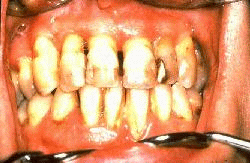

La misma paciente tres años después del tratamiento periodontal con reconstrucción de puente fijo en maxilar superior.  Las encías se muestran saludables y al sondaje  presentan un profundidad de surco  de 3 mm. Los incisivos inferiores fueron reubicados por medio de ortodoncia.